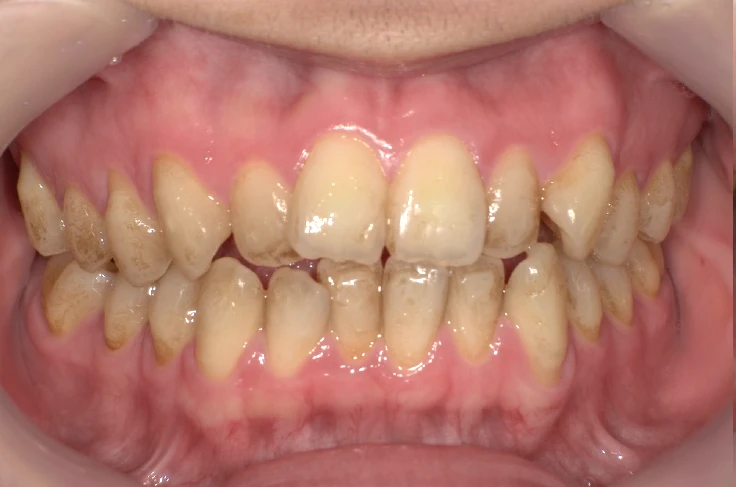

before

| 主 訴 | 着色を落としたい |

|---|---|

| 治療期間 | 通院 1回 |

| 治 療 費 | 1回 7,700〜11,000円(税込) |

| 治療内容 | PMTC |

| 治療のリスク | 歯自体の色を白くすることはできない。 しばらくすると再び着色することがある。 |